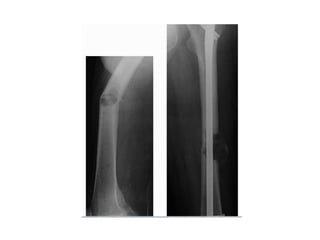

• Risk for impending fractures depends upon:

• Location of lesion

• Extent of lesion

• Osteolytic or Osteoblastic or mixed

• Primary cancer site.

• Peritrochantric femur is the most likely to cause

serious morbidity and therefore threshold for

prophylactic intervention is low

• Femur account for 65% of pathologic fracture

• Humerus and vertebra also require special

attention